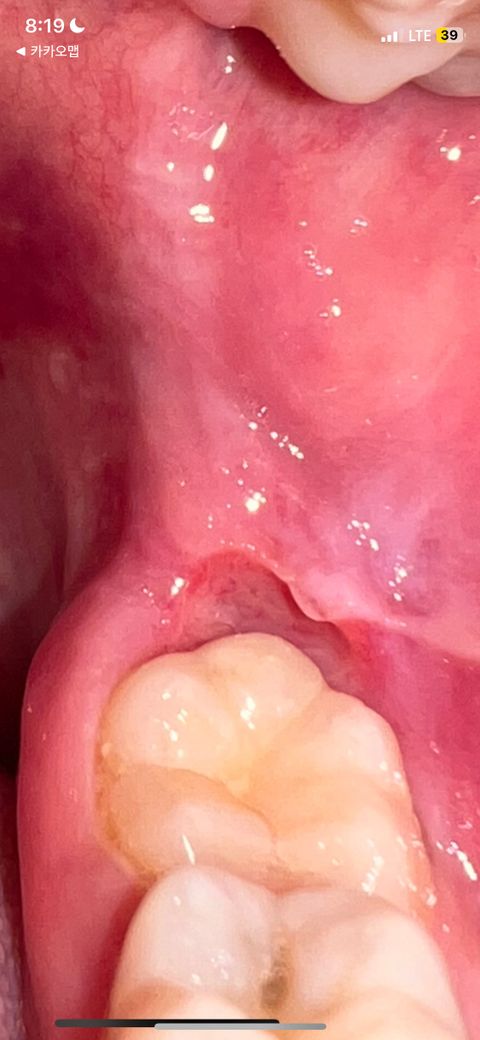

어금니 안쪽에 이렇게 파여있다고해야하나? 구내염인지 염증인지 아프고 물만마셔도 아파요 치과에가야하나요? 정확히 증상이어떤지 궁금해요

음식조절이나 알콜 안되는지도 궁금합니다

염증이 심하게 생기신거 같은데 치과에 가셔서 검진후 잇몸치료를 받아보시는게 좋을것같습니다.

보통 아래 위에 사랑니가 있다면 사랑니로 인하여 주변 잇몸이 붓거나 잇몸을 손상시켜 이러한 증상이 많이 나타나게 됩니다. 따라서 현재 사진 뿐만 아니라 주변 치아의 교합 상태 등에 대해서도 판단을 받아보셔야 하며 계속해서 불편감이 있다면 치과 방문을 권해드립니다.

해당 부위 잇몸질환 내지는 사랑니가 의심됩니다. 자극적인 음식을 피하시는 것을 추천드리고 치과에서 정확한 검진을 받아보시길 바라겠습니다.